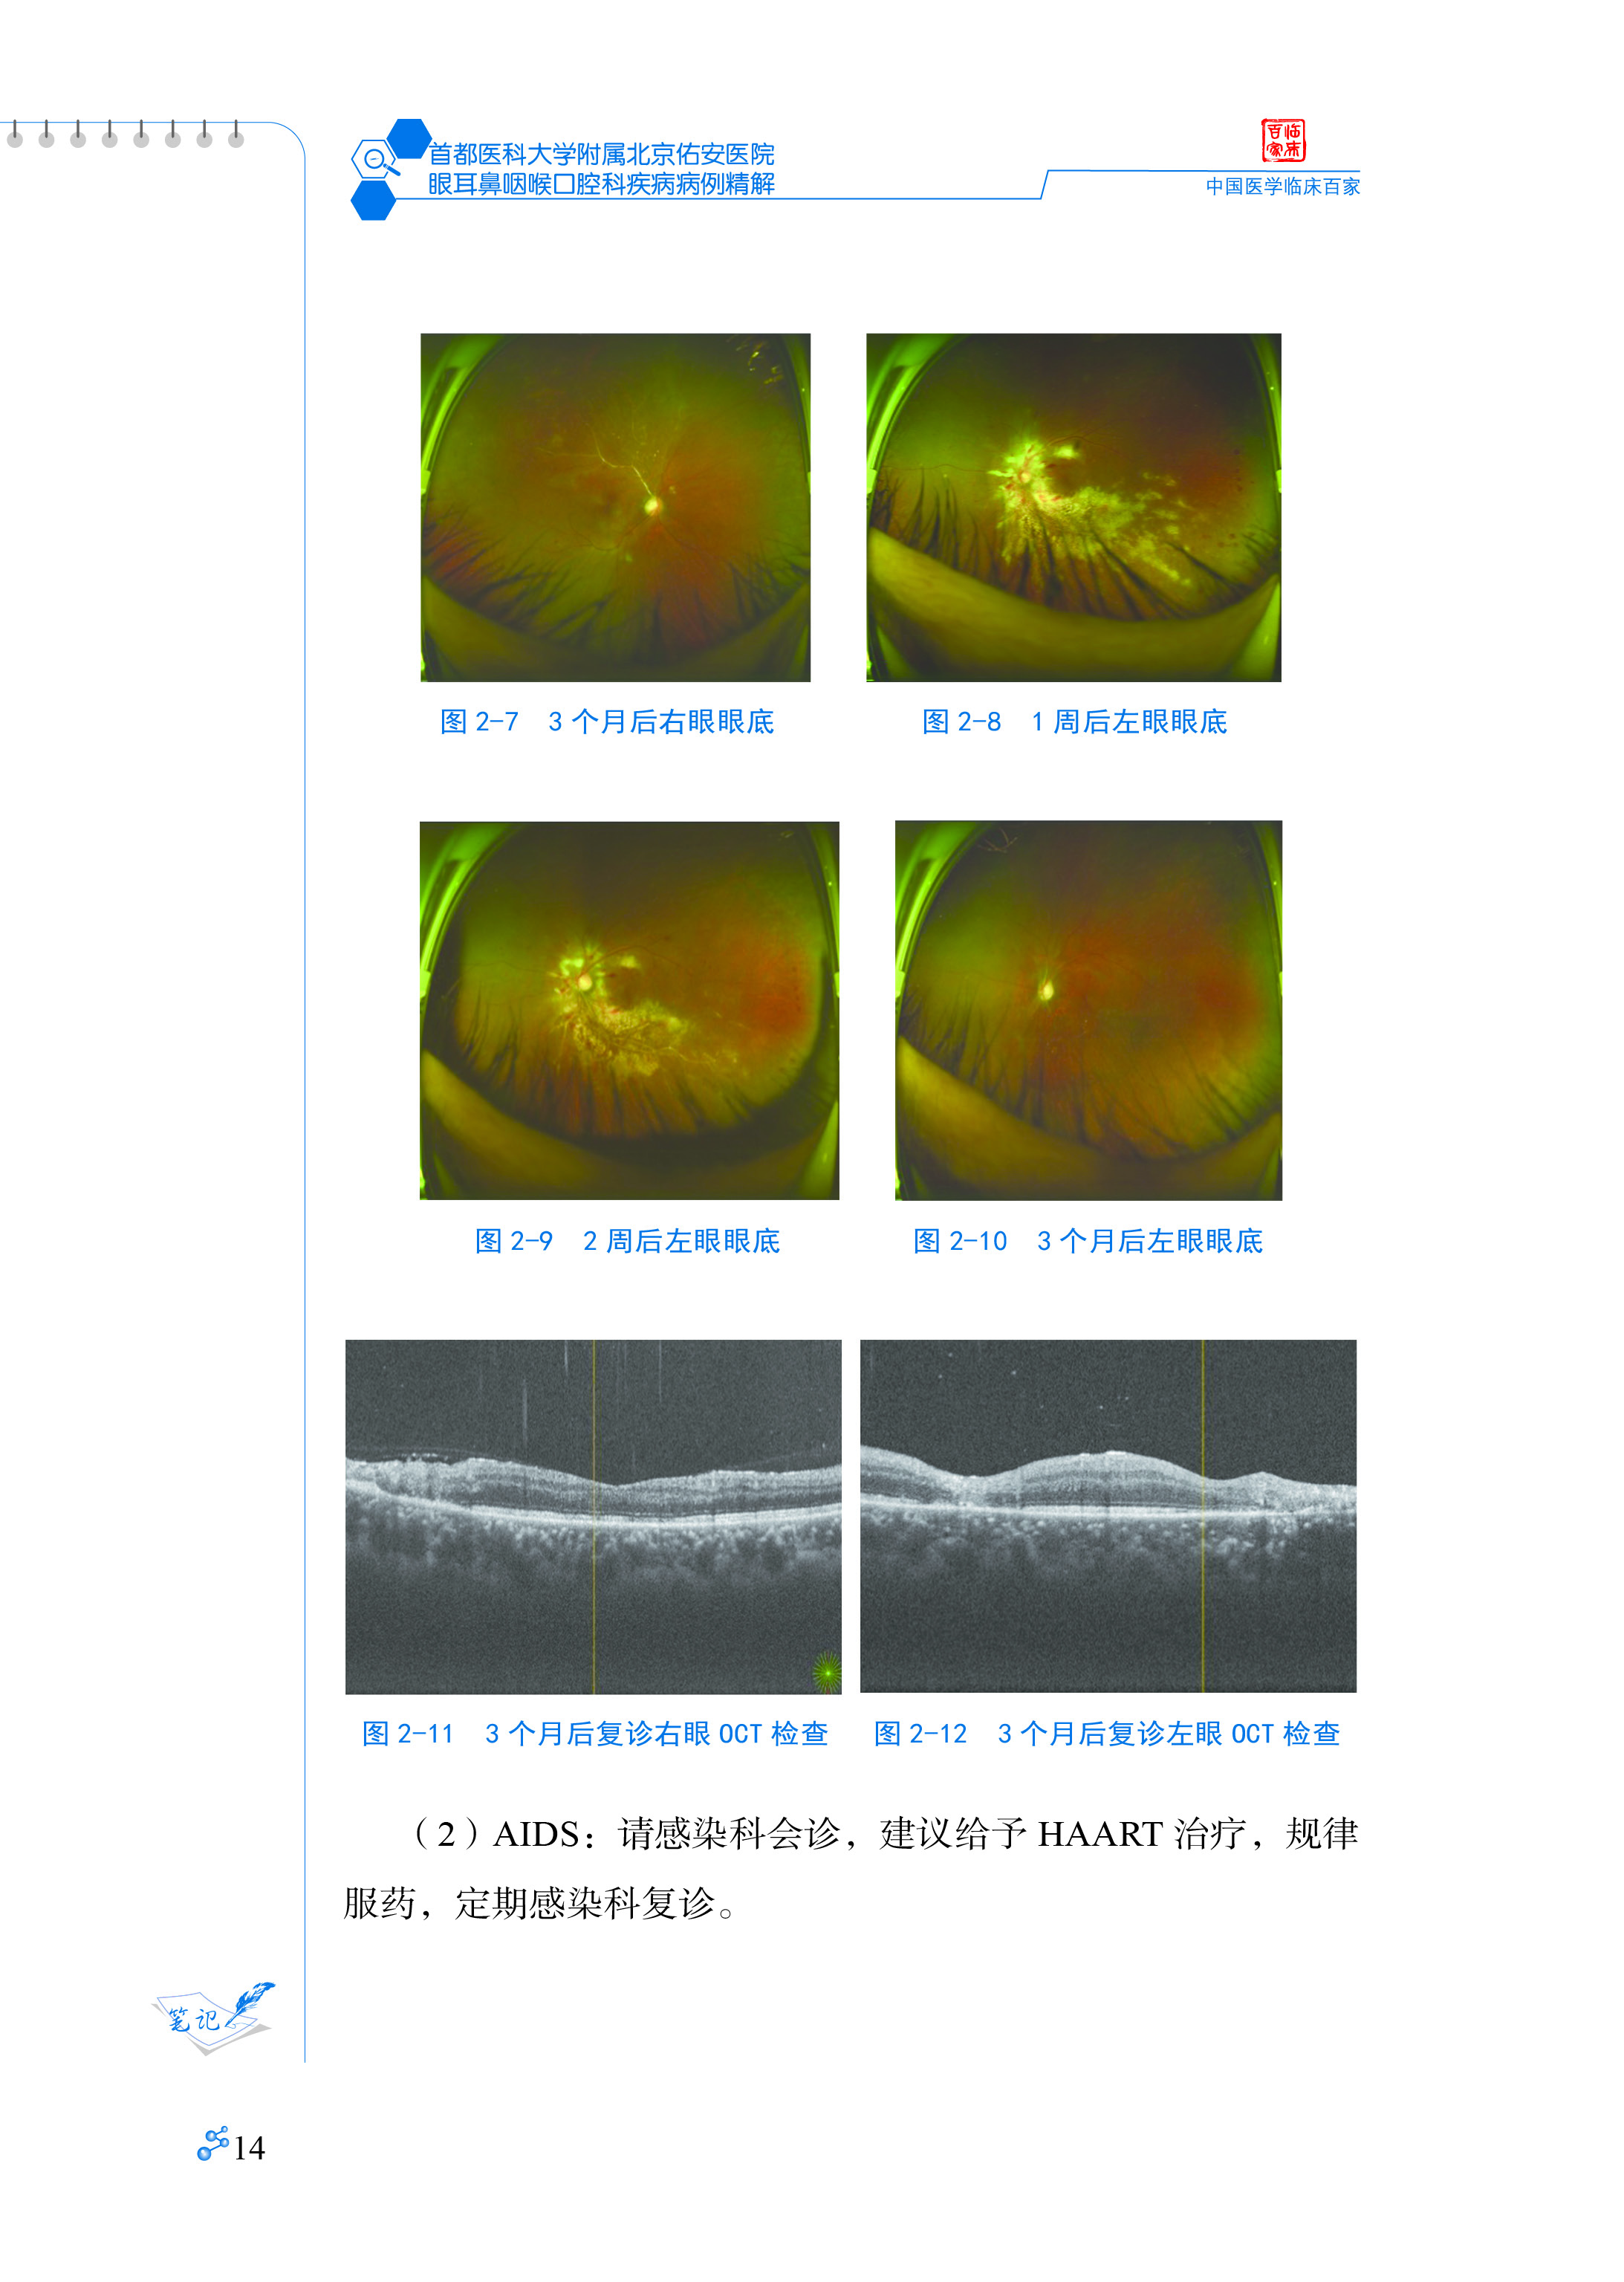

病例2 巨细胞病毒视网膜炎11

病例3 HIV相关视网膜微血管病变17